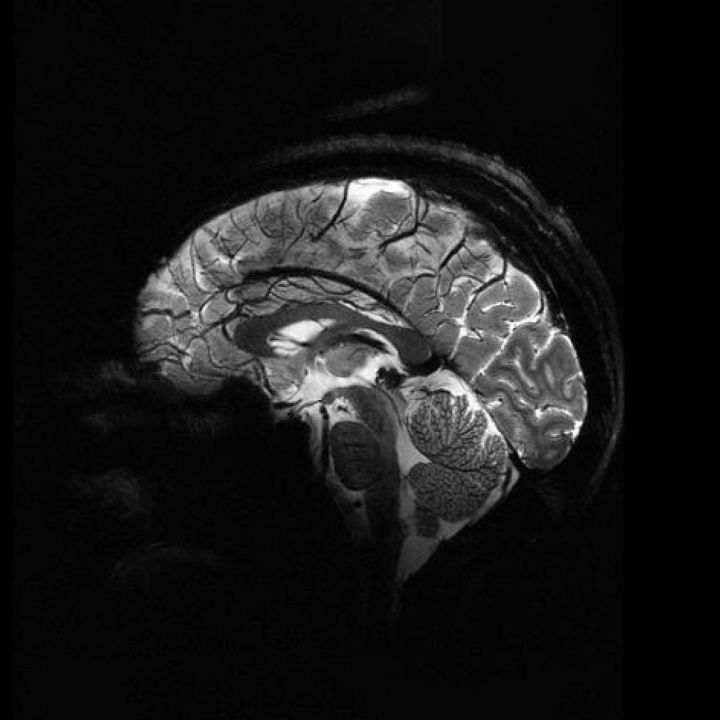

Mémoire qui flanche : l’IRM relie le « rétrécissement » du cerveau au vieillissement. - Sciences & Santé -

Mémoire qui flanche : l’IRM relie le « rétrécissement » du cerveau au vieillissement.